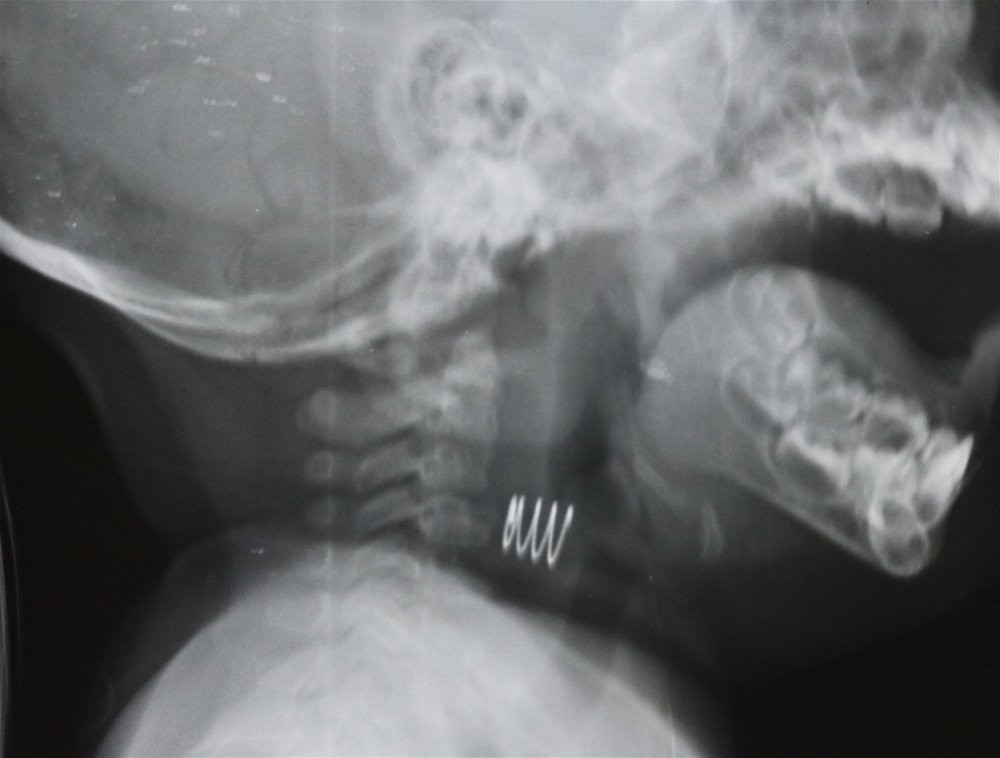

Dị vật hình dạng lò xo được phim chụp Xquang chỉ rõ vị trí (Ảnh: BVCC)

Bệnh viện Việt Nam Thụy Điển Uông Bí (Quảng Ninh) cho biết, bệnh viện vừa xử trí một ca trẻ nhỏ bị hóc dị vật. Dị vật được lấy ra là một chiếc lò xo có có 2 đầu sắc nhọn han gỉ với khoảng 3,5 vòng cuộn, đường kính 0,8 cm.